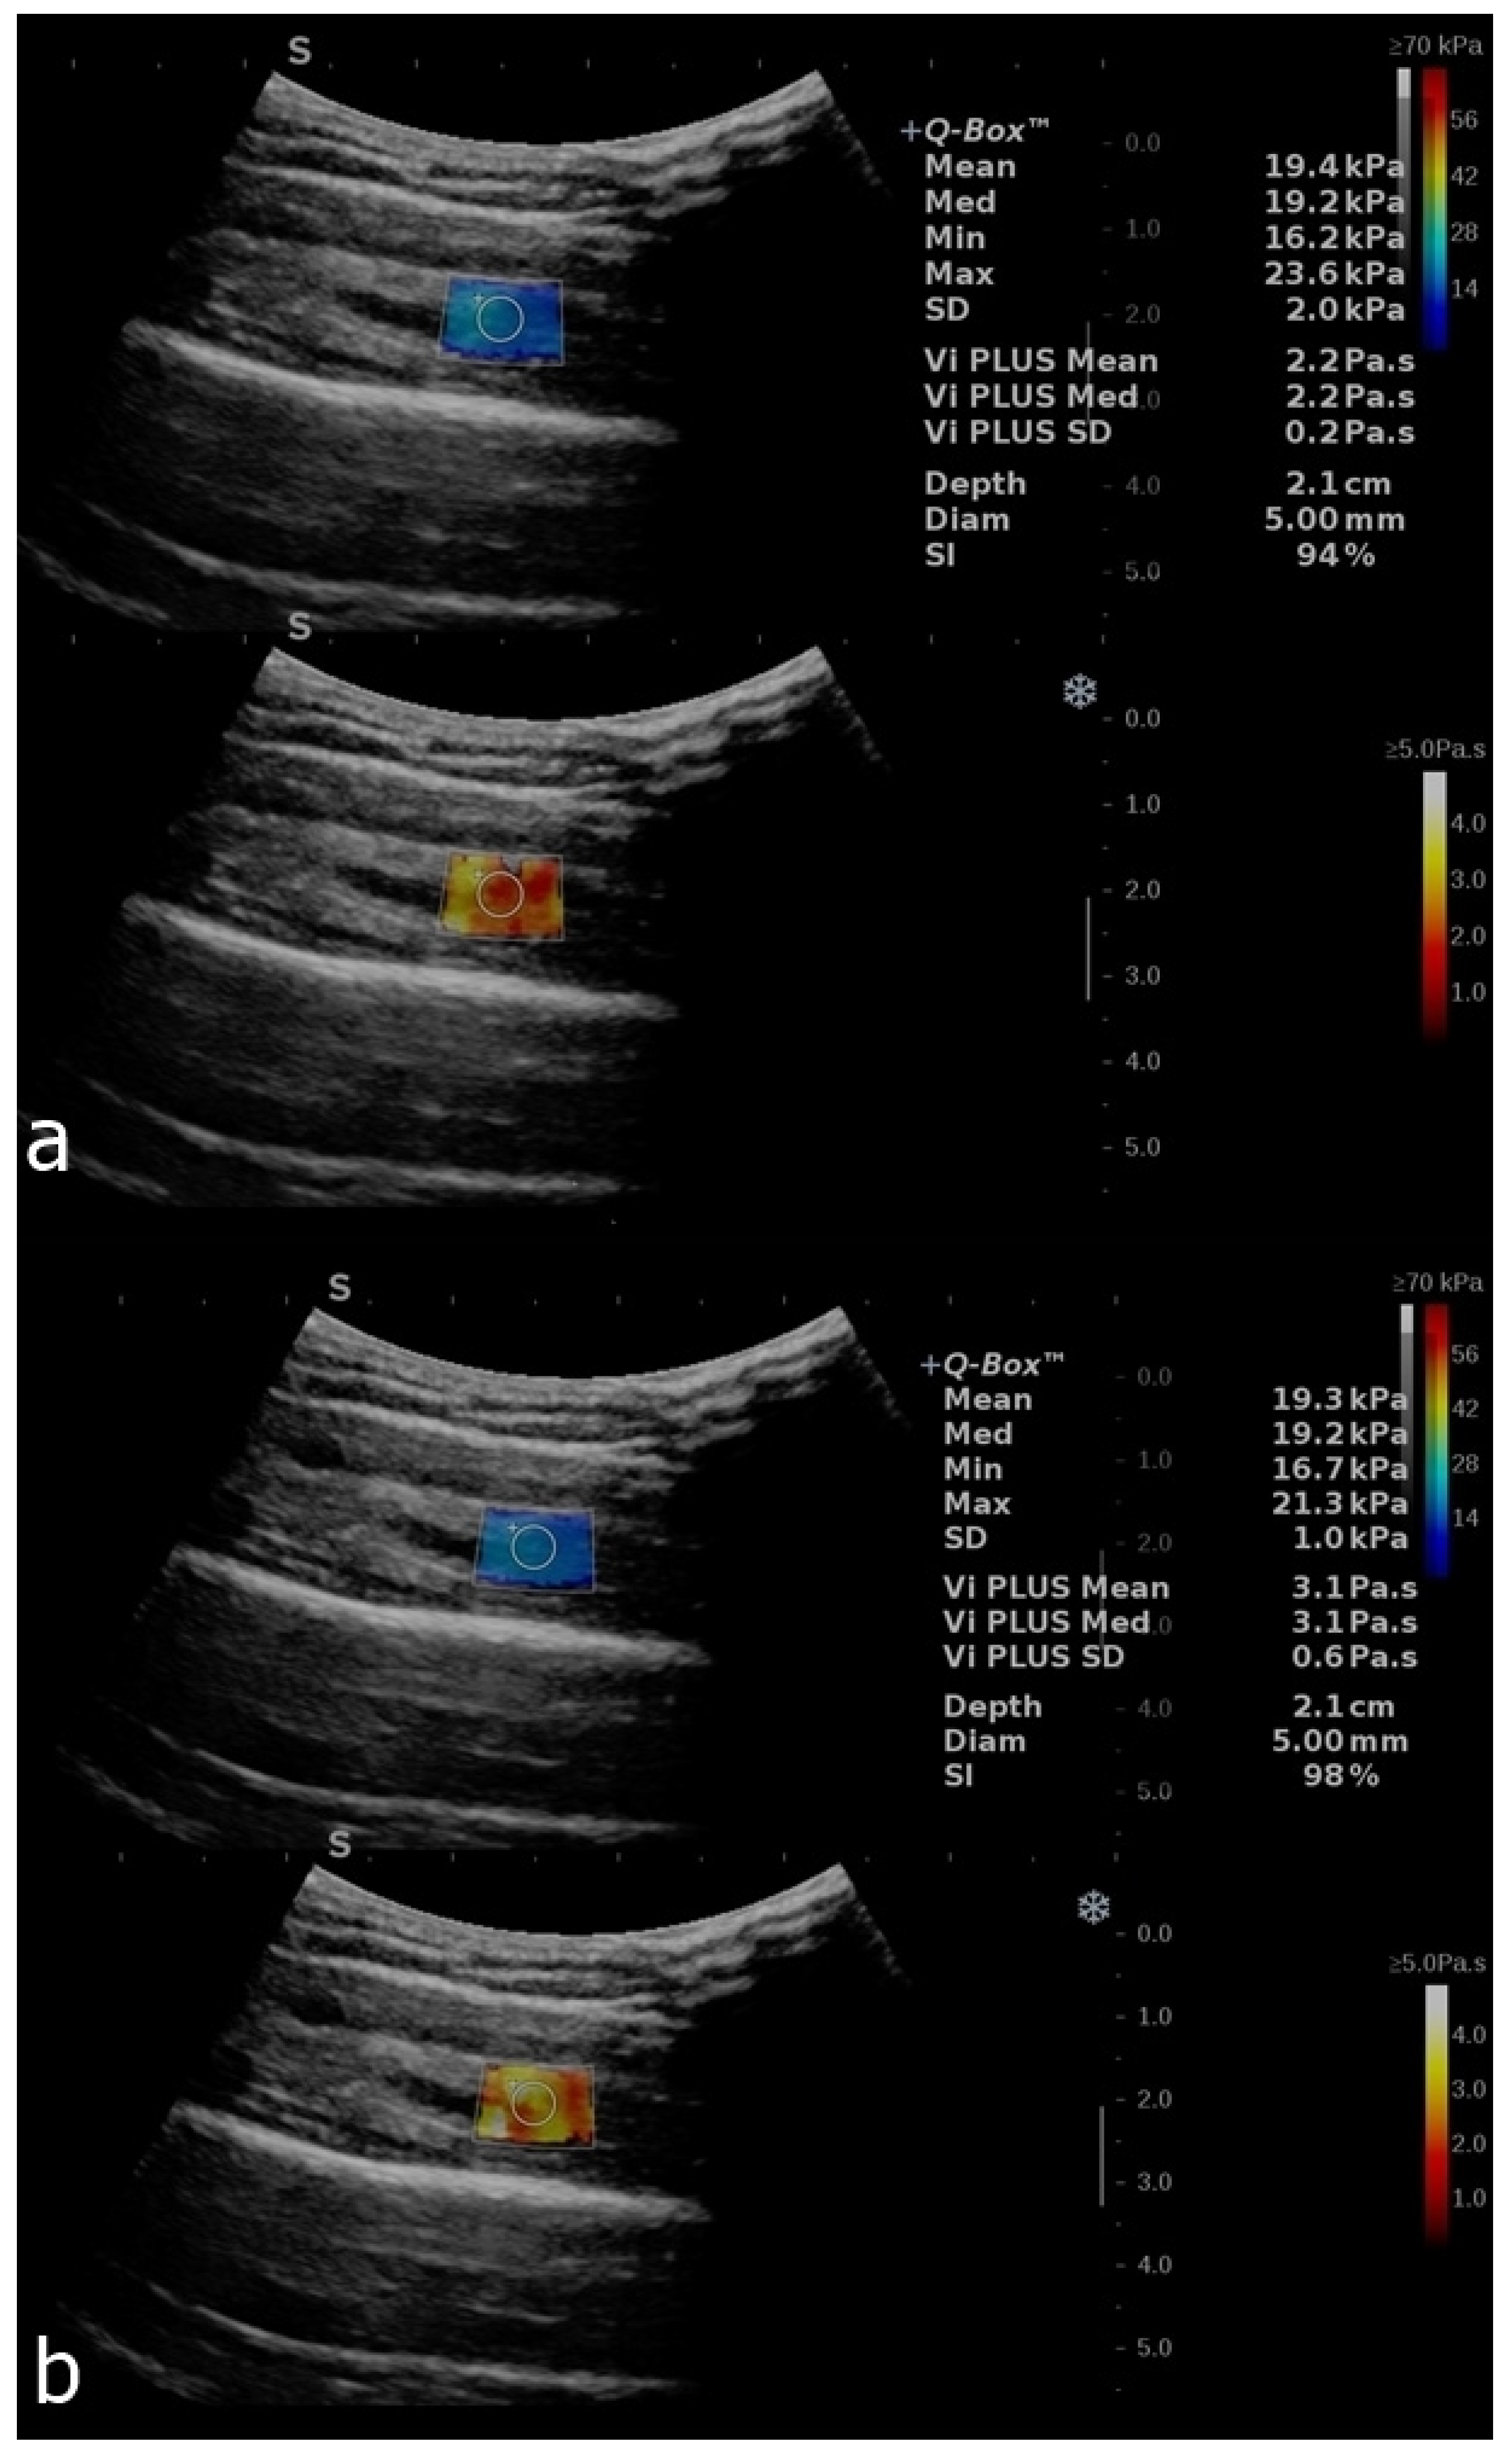

Figure 3.

B-mode image with an elastogram of the deltoid muscle in a healthy volunteer. Longitudinal plans of the deltoid muscle as follows: relaxed (a) and after contraction (b). The regions of interest (ROIs) were placed in the box when the homogenous coloring of the box was obtained with a stability index of over 90%. The top image in each set reflects the SWE mode, and the bottom image reflects the ViPLUS application. ROI values are expressed in kPa for SWE and Pa.s for ViPLUS.